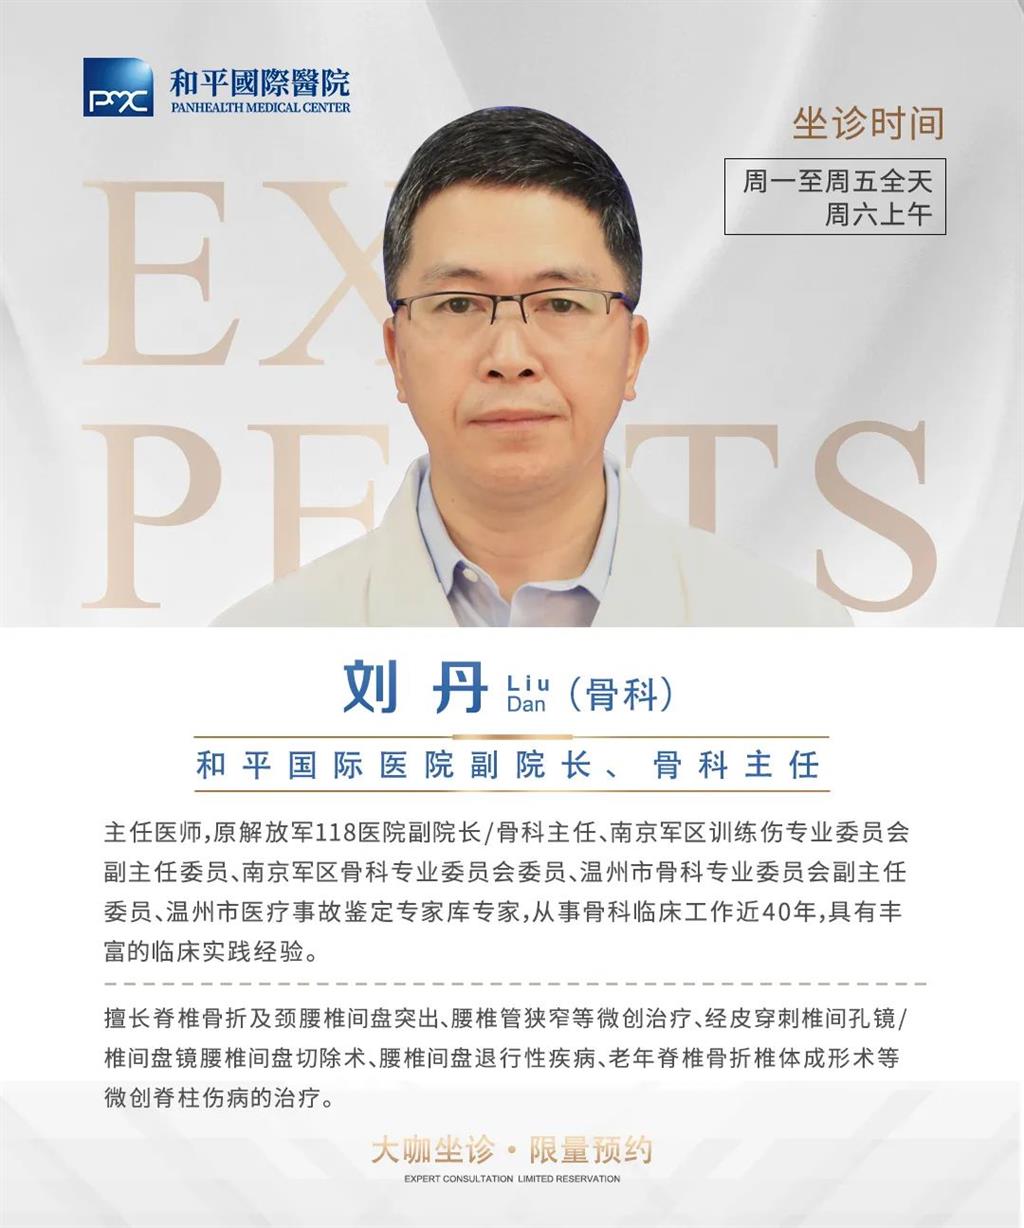

據(jù)了解,脊柱內(nèi)鏡下腰椎融合術(shù)只需要打幾個(gè)“鑰匙孔”即可完成。聽起來是不是很簡(jiǎn)單?在脊柱內(nèi)鏡下,劉丹主任先后為患者進(jìn)行了椎管減壓、椎間盤摘除,再實(shí)施椎弓根螺釘放置、椎體植骨融合內(nèi)固定,一系列步驟有條不紊。

看似簡(jiǎn)單的幾個(gè)步驟,但實(shí)際上很復(fù)雜,需要主刀醫(yī)生有豐富的手術(shù)經(jīng)驗(yàn)和細(xì)致耐心的操作。

劉丹主任表示,傳統(tǒng)手術(shù)需要廣泛剝離脊椎兩側(cè)的肌肉,術(shù)后容易產(chǎn)生疤痕、肌肉萎縮、腰部疼痛等;術(shù)中出血多,往往需要額外輸血,另外創(chuàng)傷大的同時(shí)也容易破壞脊椎的正常結(jié)構(gòu),對(duì)于老年人、體弱的人群來講,恢復(fù)期長(zhǎng)、風(fēng)險(xiǎn)多。

而脊柱內(nèi)鏡下腰椎融合術(shù),作為目前國(guó)內(nèi)脊柱微創(chuàng)領(lǐng)域大力發(fā)展的新技術(shù),徹底改變了傳統(tǒng)開刀椎板切除椎間植骨融合內(nèi)固定的大創(chuàng)傷現(xiàn)狀,可以在較大程度上減少對(duì)脊柱后方穩(wěn)定結(jié)構(gòu)的破壞,創(chuàng)傷小,出血少,術(shù)后恢復(fù)快。

非常適用于體質(zhì)較差不能耐受開放手術(shù)的老年患者,且手術(shù)全程均在內(nèi)鏡監(jiān)測(cè)下進(jìn)行,能夠最大程度地避免硬膜囊和神經(jīng)根損傷,手術(shù)安全性更高。

術(shù)中只需切開4個(gè)如“鑰匙孔”般大小的孔道